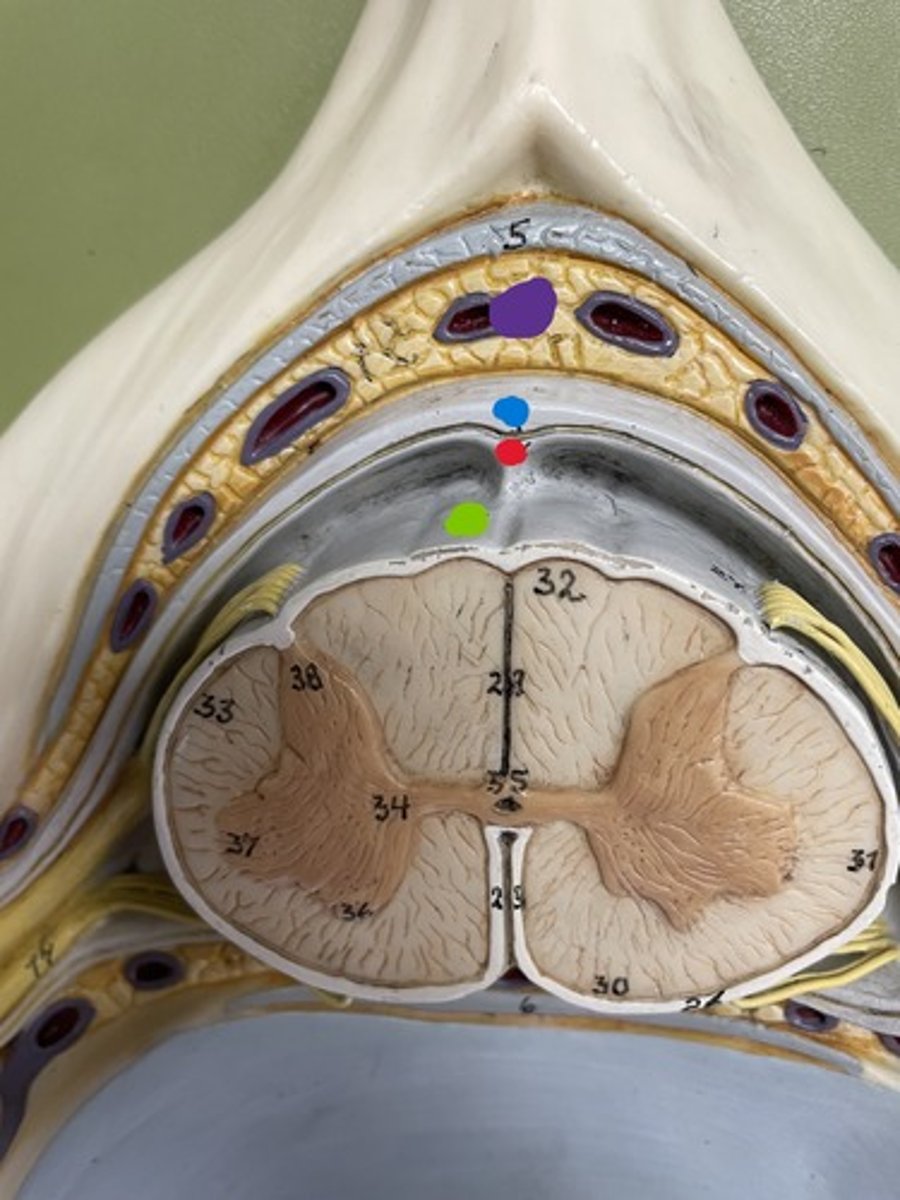

Dura mater

blue

Arachnoid mater

red

Pia mater

green

Epidural space

purple

Subdural space

between red and blue

Subarachnoid space

between red and green